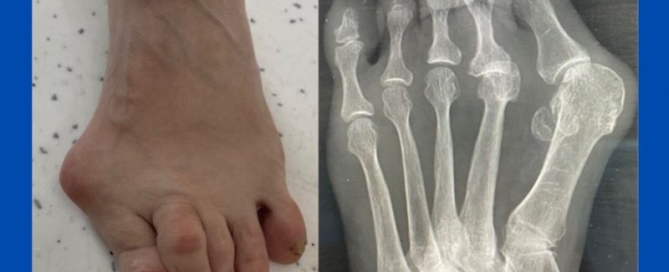

Gout

Blog's main page I have carried out surgery on three patients recently who have had moderate bunions on X-ray, however, clinically they appear to be much worse. On X-ray, you [...]